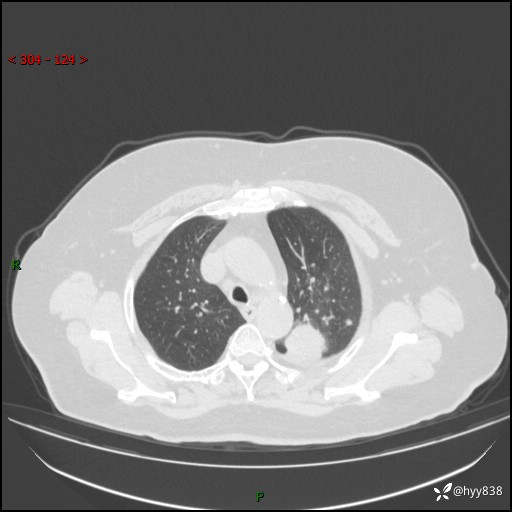

老年女性,左上肺结节8年。典型又不典型,看你如何解读---结果公布(值得分析)

主诉:检查发现左上肺结节8年,较前增大。

简要病史:患者于8年前体检行胸部CT检查发现左上肺结节(4mm),患者平素间断咳嗽咳痰,无心慌、胸闷、胸痛、呼吸困难、低热、盗汗,无头痛、头晕,无腹痛、腹胀等不适,未行特殊处理,定期复查。2023-09-21胸部CT示左上肺结节(2cm)较前增大,2024-02-01胸部CT示左上肺尖后段(39*32mm),左侧肺门及纵隔淋巴结增大,现患者欲求手术治疗,遂来我院就诊,以“左上肺结节”收入我科。 患者自起病以来,精神可,睡眠可,饮食可,大小便正常,体重无明显改变。

辅助检查:CT

胸部CT平扫